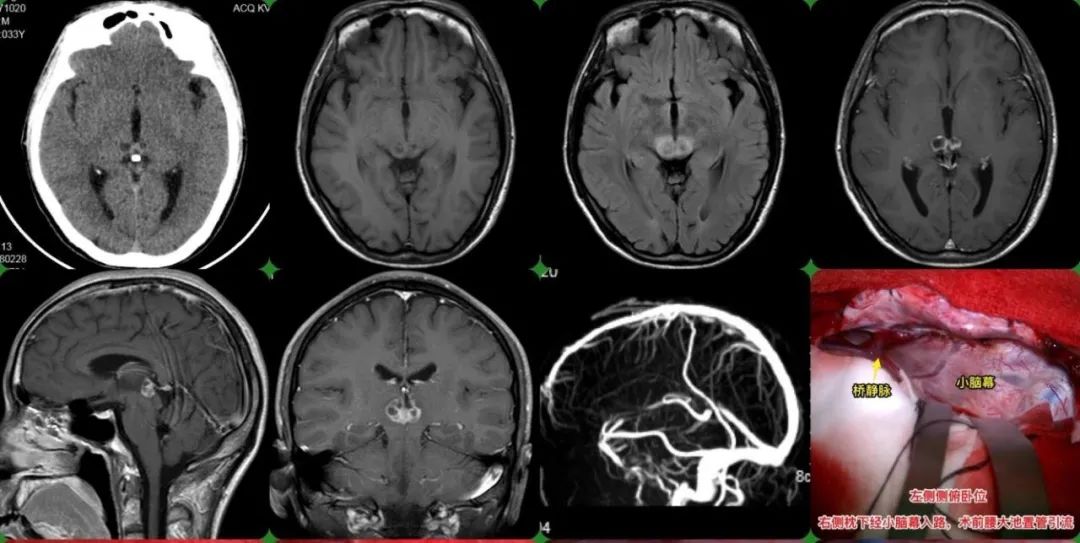

Zhaotong man's vision is blurry and double vision, the test results Blurry Vision Brain Tumor How do brain tumors cause eye problems?. Blurred vision (you may find it difficult to watch tv or read) ‘greying out’. Brain tumors can lead to vision problems such as: Prompt treatment may help restore or stop vision loss from progressing. Double vision may be very obvious, or may appear as blurred vision. The location or type of a brain. Blurry Vision Brain Tumor.